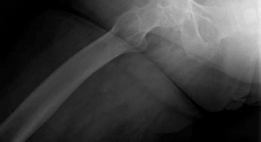

Clinical & Radiographic Imaging